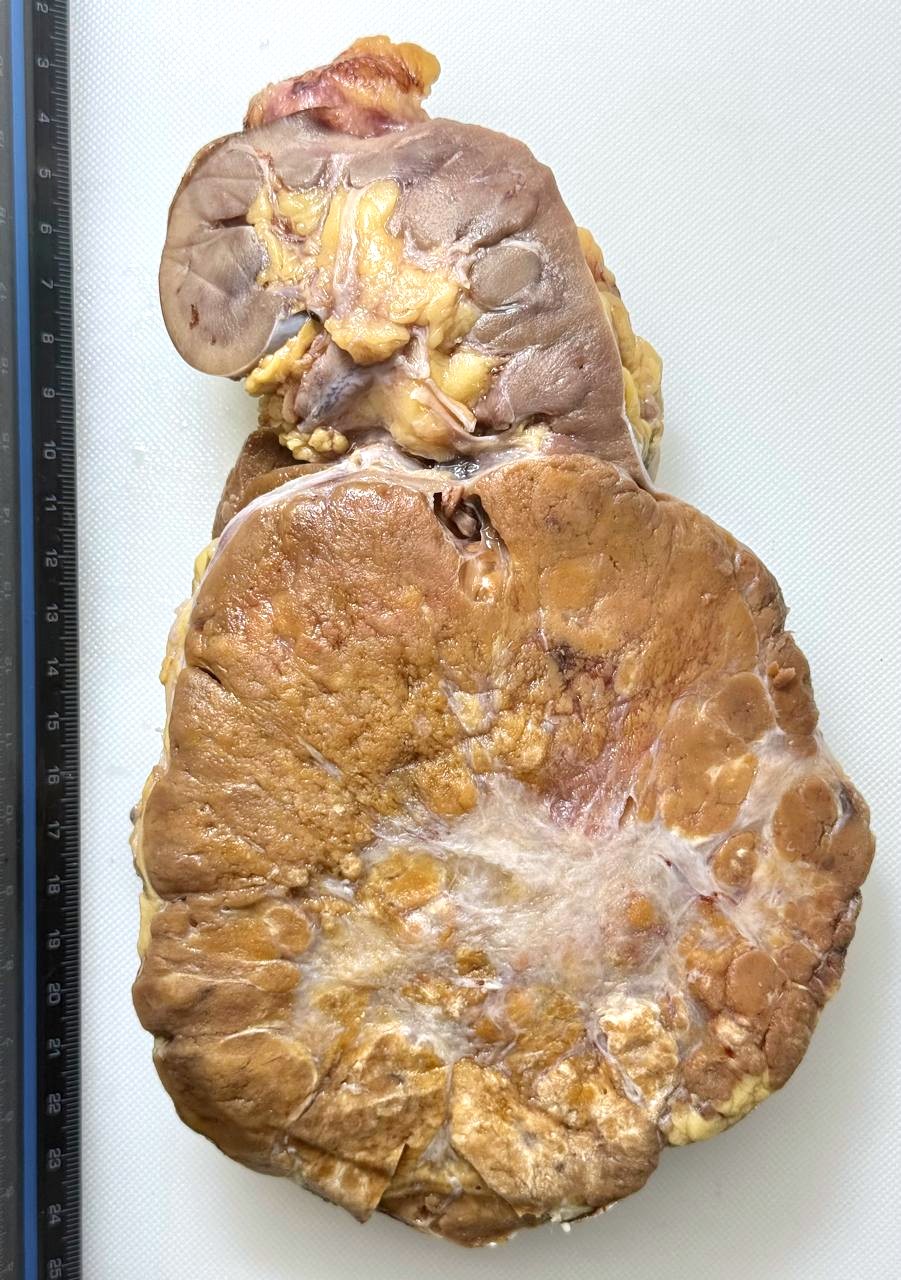

Patología Molecular

El diagnóstico sobre muestras de tejidos y líquidos corporales en plena era de la medicina del futuro, está basado en la integración de técnicas y conocimientos diferentes.

Hoy más que nunca es importante integrar una buena historia clínica con un correcto estudio de imagen y una buena morfología que además puede estar apoyada con proceso especiales complementarios relacionados con la Inmunología, Biología Molecular y Citogenética, generando así un estudio integral conocido como Patología Molecular.